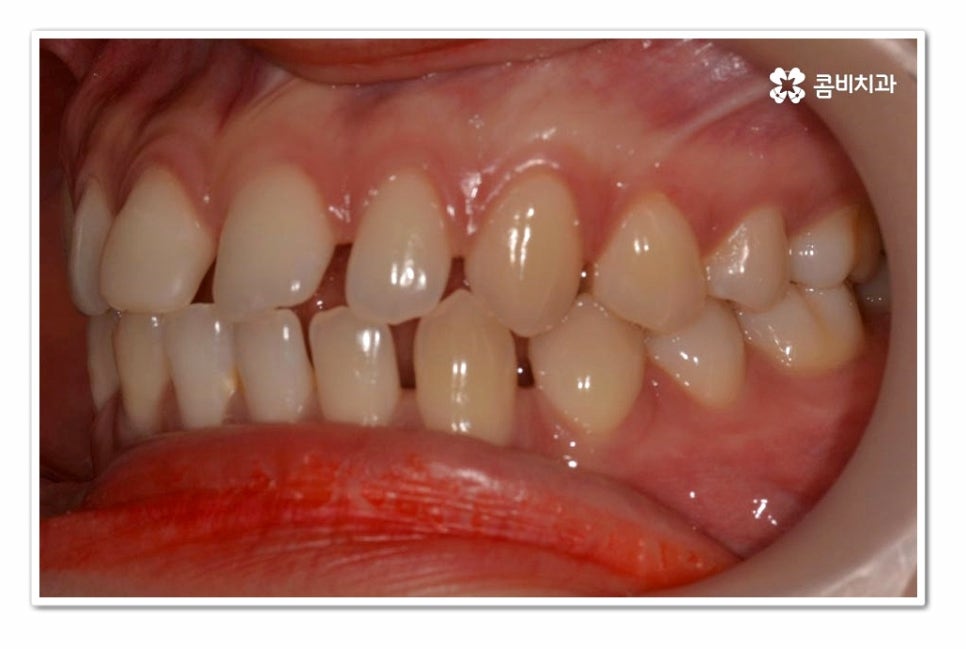

위 환자분의 경우 치아교정을 통해서 앞니 벌어짐 치료를 진행한 사례이며

치아의 이동 공간과 교합을 고려할 때 전체교정이 필요했던 사례라고 할 수 있어요.

위 환자분의 경우 윗니 만이 아니라 아랫니도 벌어져 있기 때문에

라미네이트와 같이 단기적으로 심미성을 고려한 치료보다는

치아교정을 통해 치아의 건강부터 교합, 심미성을 함께

개선할 수 있는 치료 계획을 세운 것이라 할 수 있어요.